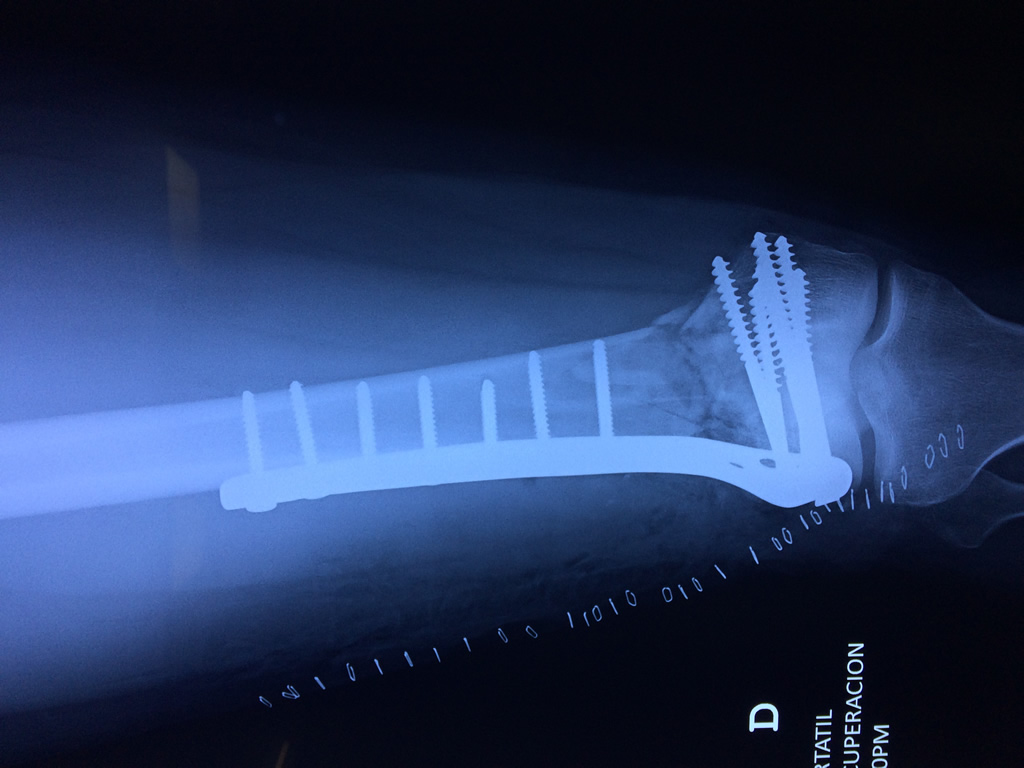

Cirugías de Hombros - Fémur

El fémur es el hueso del muslo, el segundo segmento del miembro inferior. Es el hueso más largo, fuerte y voluminoso del cuerpo humano.